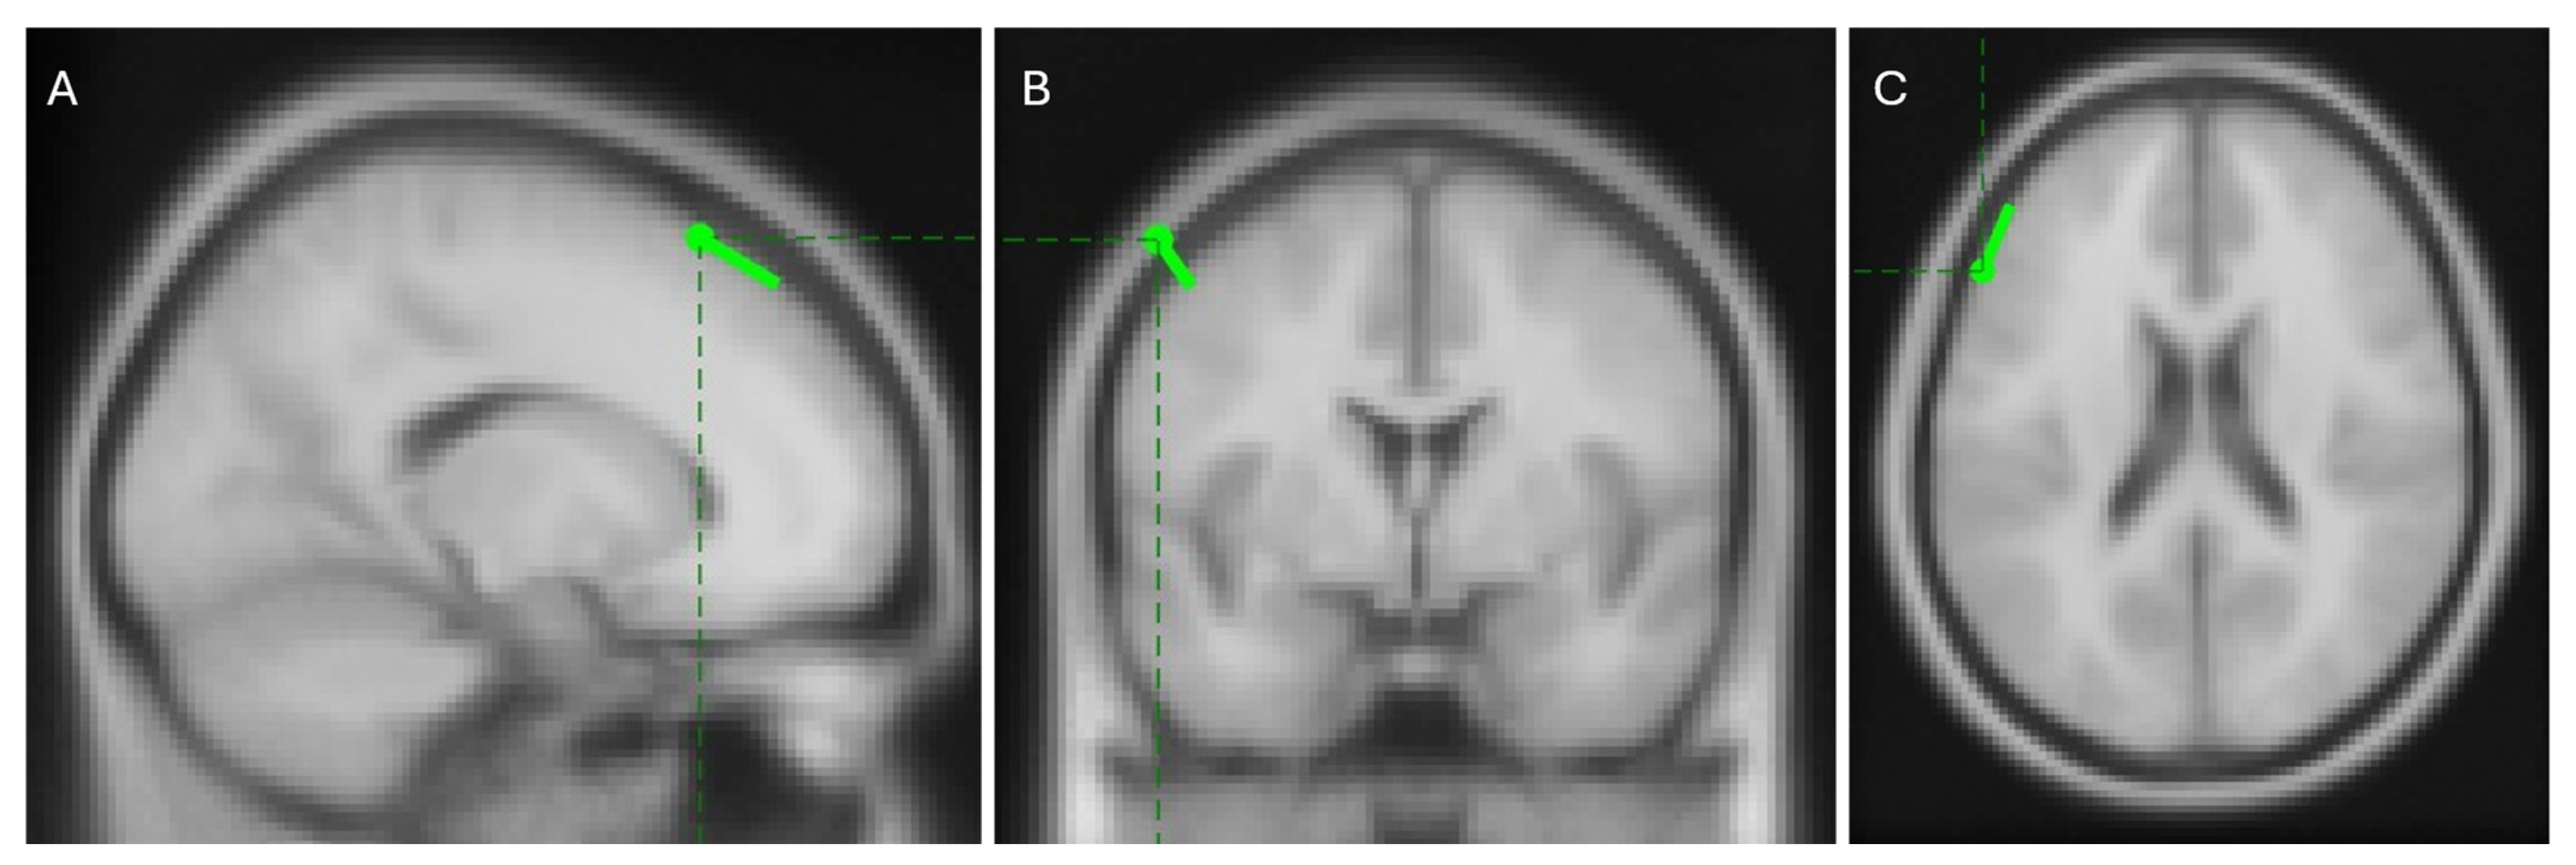

Among these sources, the one with the highest PLV, shown as the left-most map in Figure 13, is expected to represent a clear dipolar source located in the brain cortex contralateral to the movement. Localization with the FieldTrip toolbox places this source in the left caudal middle frontal area, as shown in Figure 14. This region is well-documented for its role in manual control [56,57,58,59,60] and its contralateral location aligns with the known physiology of human motor function [61]. These results support the hypothesis that phase synchrony is a strong candidate for explaining corticomuscular control.

Figure 14.

Sagittal (A), coronal (B), and transversal (C) views of the localization of the most synchronous source situated in the left caudal middle frontal area. Images present standard magnetic resonance slices which are not fixed at the dipole position.